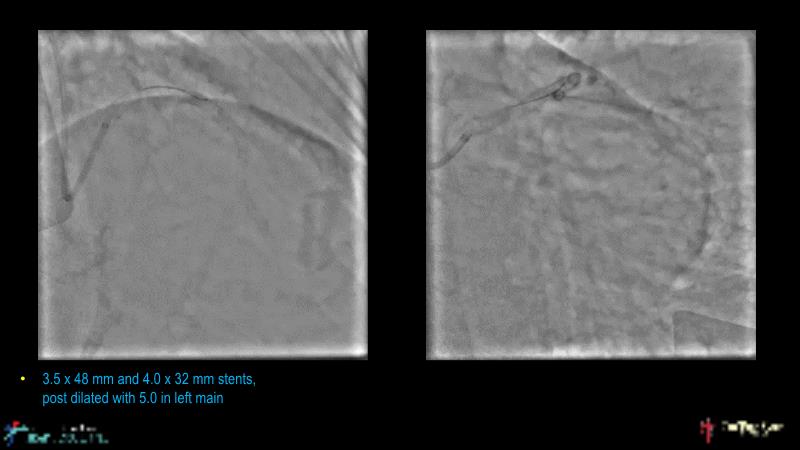

This session is recommended for you if you are seeking insights into the advantages of using IVUS imaging over visual assessment for better outcomes in left main bifurcation procedures. Discuss with experts the benefits of using RotaCUT in lesion preparation for left main bifurcation and explore the impact of high radial strength stents on the procedure's success.

• To know how a high radial strength stent can make a difference in left main bifurcation